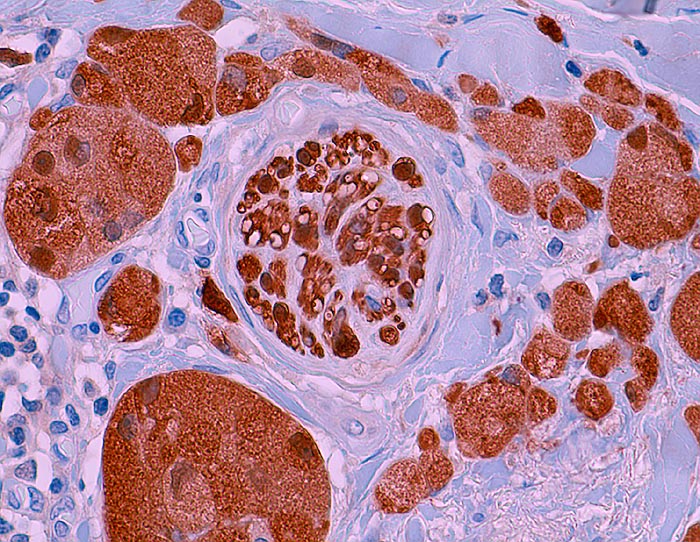

Granularzelltumor

Gruppen von Tumorzellen angeordnet um einen peripheren Nervenast.

Infiltrate eines Granularzelltumors in einem Lymphknoten entsprechen keinem Malignitätskriterium.

Histologisch sehen benigne und maligne Granularzelltumoren fast gleich aus. Hinweise auf mögliches malignes Verhalten: hohe Zellularität, kleinere längliche Zellen, mehr als 1 Mitose pro 10 HPF, Rezidiv, rasches Wachstum, grösser als 5cm.

Histologie

Immunhistochemie

S-100